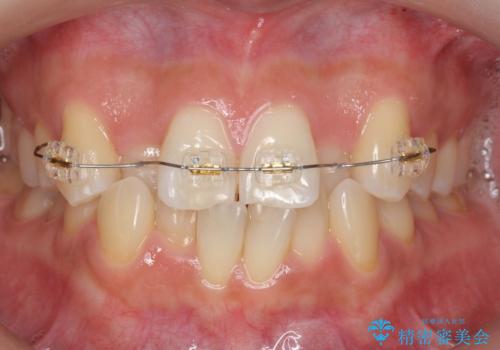

- 矯正装置

- インビザライン

上はワイヤー部分矯正、下はインビザライン(マウスピース)で部分矯正を行いました。